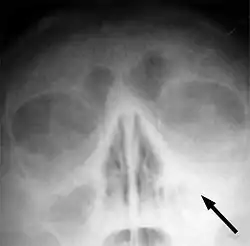

![]() يشير السهم إلى منطقة الالتهاب في جيوب الفك العلوي في الجانب الأيسر من الوجه. لاحظ أن المنطقة التى يشير لها السهم ليست شفافه لقلة الهواء فيها، مما يشير إلى امتلائها بالسوائل بالمقارنه مع الجانب الآخر من الوجه. يشير السهم إلى منطقة الالتهاب في جيوب الفك العلوي في الجانب الأيسر من الوجه. لاحظ أن المنطقة التى يشير لها السهم ليست شفافه لقلة الهواء فيها، مما يشير إلى امتلائها بالسوائل بالمقارنه مع الجانب الآخر من الوجه. | |